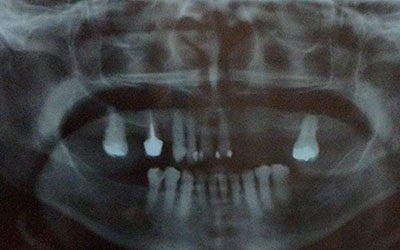

Este procedimiento requiere, en primer lugar, que tomemos los registros de la boca del paciente a través de una tomografía cone beam la cual se transfiere a el software que se encarga de proyectar la prótesis a través de la reproducción digital en 3D y obtener el mejor diagnóstico.

En el mismo software se realiza la planificación para la colocación de los implantes colocando virtualmente los implantes en la zona favorable y de esta manera se realiza una guía quirúrgica.